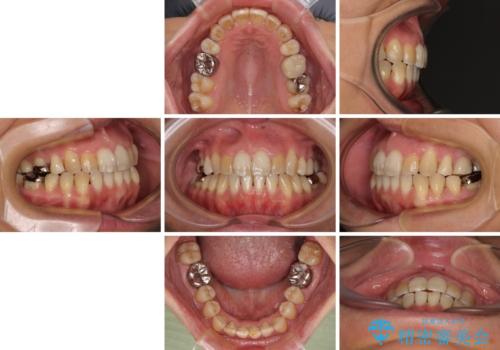

前歯の後戻り インビザラインでの再矯正治療

舌のトレーニングをしっかりと行ってくださり、10ヶ月で希望通りの歯列となりました。

日頃から飲まれる飲み物の影響で着色しやすいため、来院の度に着色除去のクリーニングも行っていました。